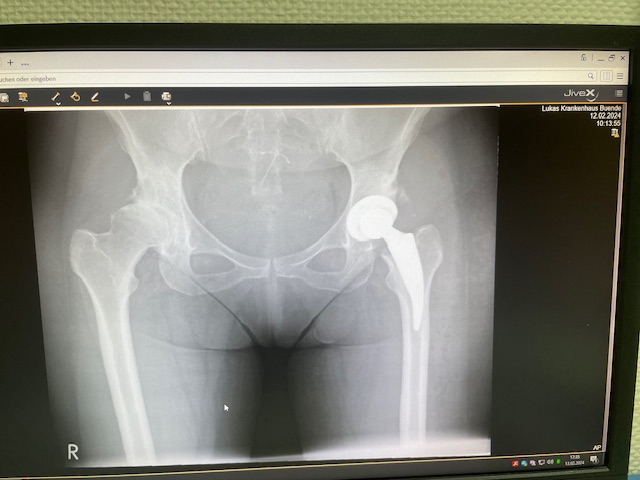

Κατά τη διάρκεια της επέμβασης, έγινε προσεκτική προετοιμασία της κοτύλης και τοποθετήθηκε εξατομικευμένο κύπελλο με ιδανική κλίση και στροφή, εξασφαλίζοντας σταθερότητα και σωστή άρθρωση με τη μηριαία κεφαλή. Ακολούθως, προετοιμάστηκε το μηριαίο οστό με βάση τον προεγχειρητικό ψηφιακό σχεδιασμό και τοποθετήθηκε το κατάλληλο βραχύ στέλεχος, μη τσιμεντούμενο στη μορφολογία του οστού της ασθενούς.

Η ακριβής εφαρμογή του προεγχειρητικού ψηφιακού σχεδιασμού επιβεβαιώθηκε διεγχειρητικά, επιτυγχάνοντας άριστη σταθερότητα της άρθρωσης και πλήρη ισοσκελισμό των κάτω άκρων. Η κινητικότητα ελέγχθηκε σε όλο το εύρος κίνησης, χωρίς σημεία αστάθειας ή πρόσκρουσης.

Η επέμβαση ολοκληρώθηκε χωρίς επιπλοκές, με ελάχιστη απώλεια αίματος και πολύ καλή άμεση σταθερότητα των εμφυτευμάτων. Η ασθενής κινητοποιήθηκε την ίδια ημέρα, με τη βοήθεια φυσικοθεραπευτή.